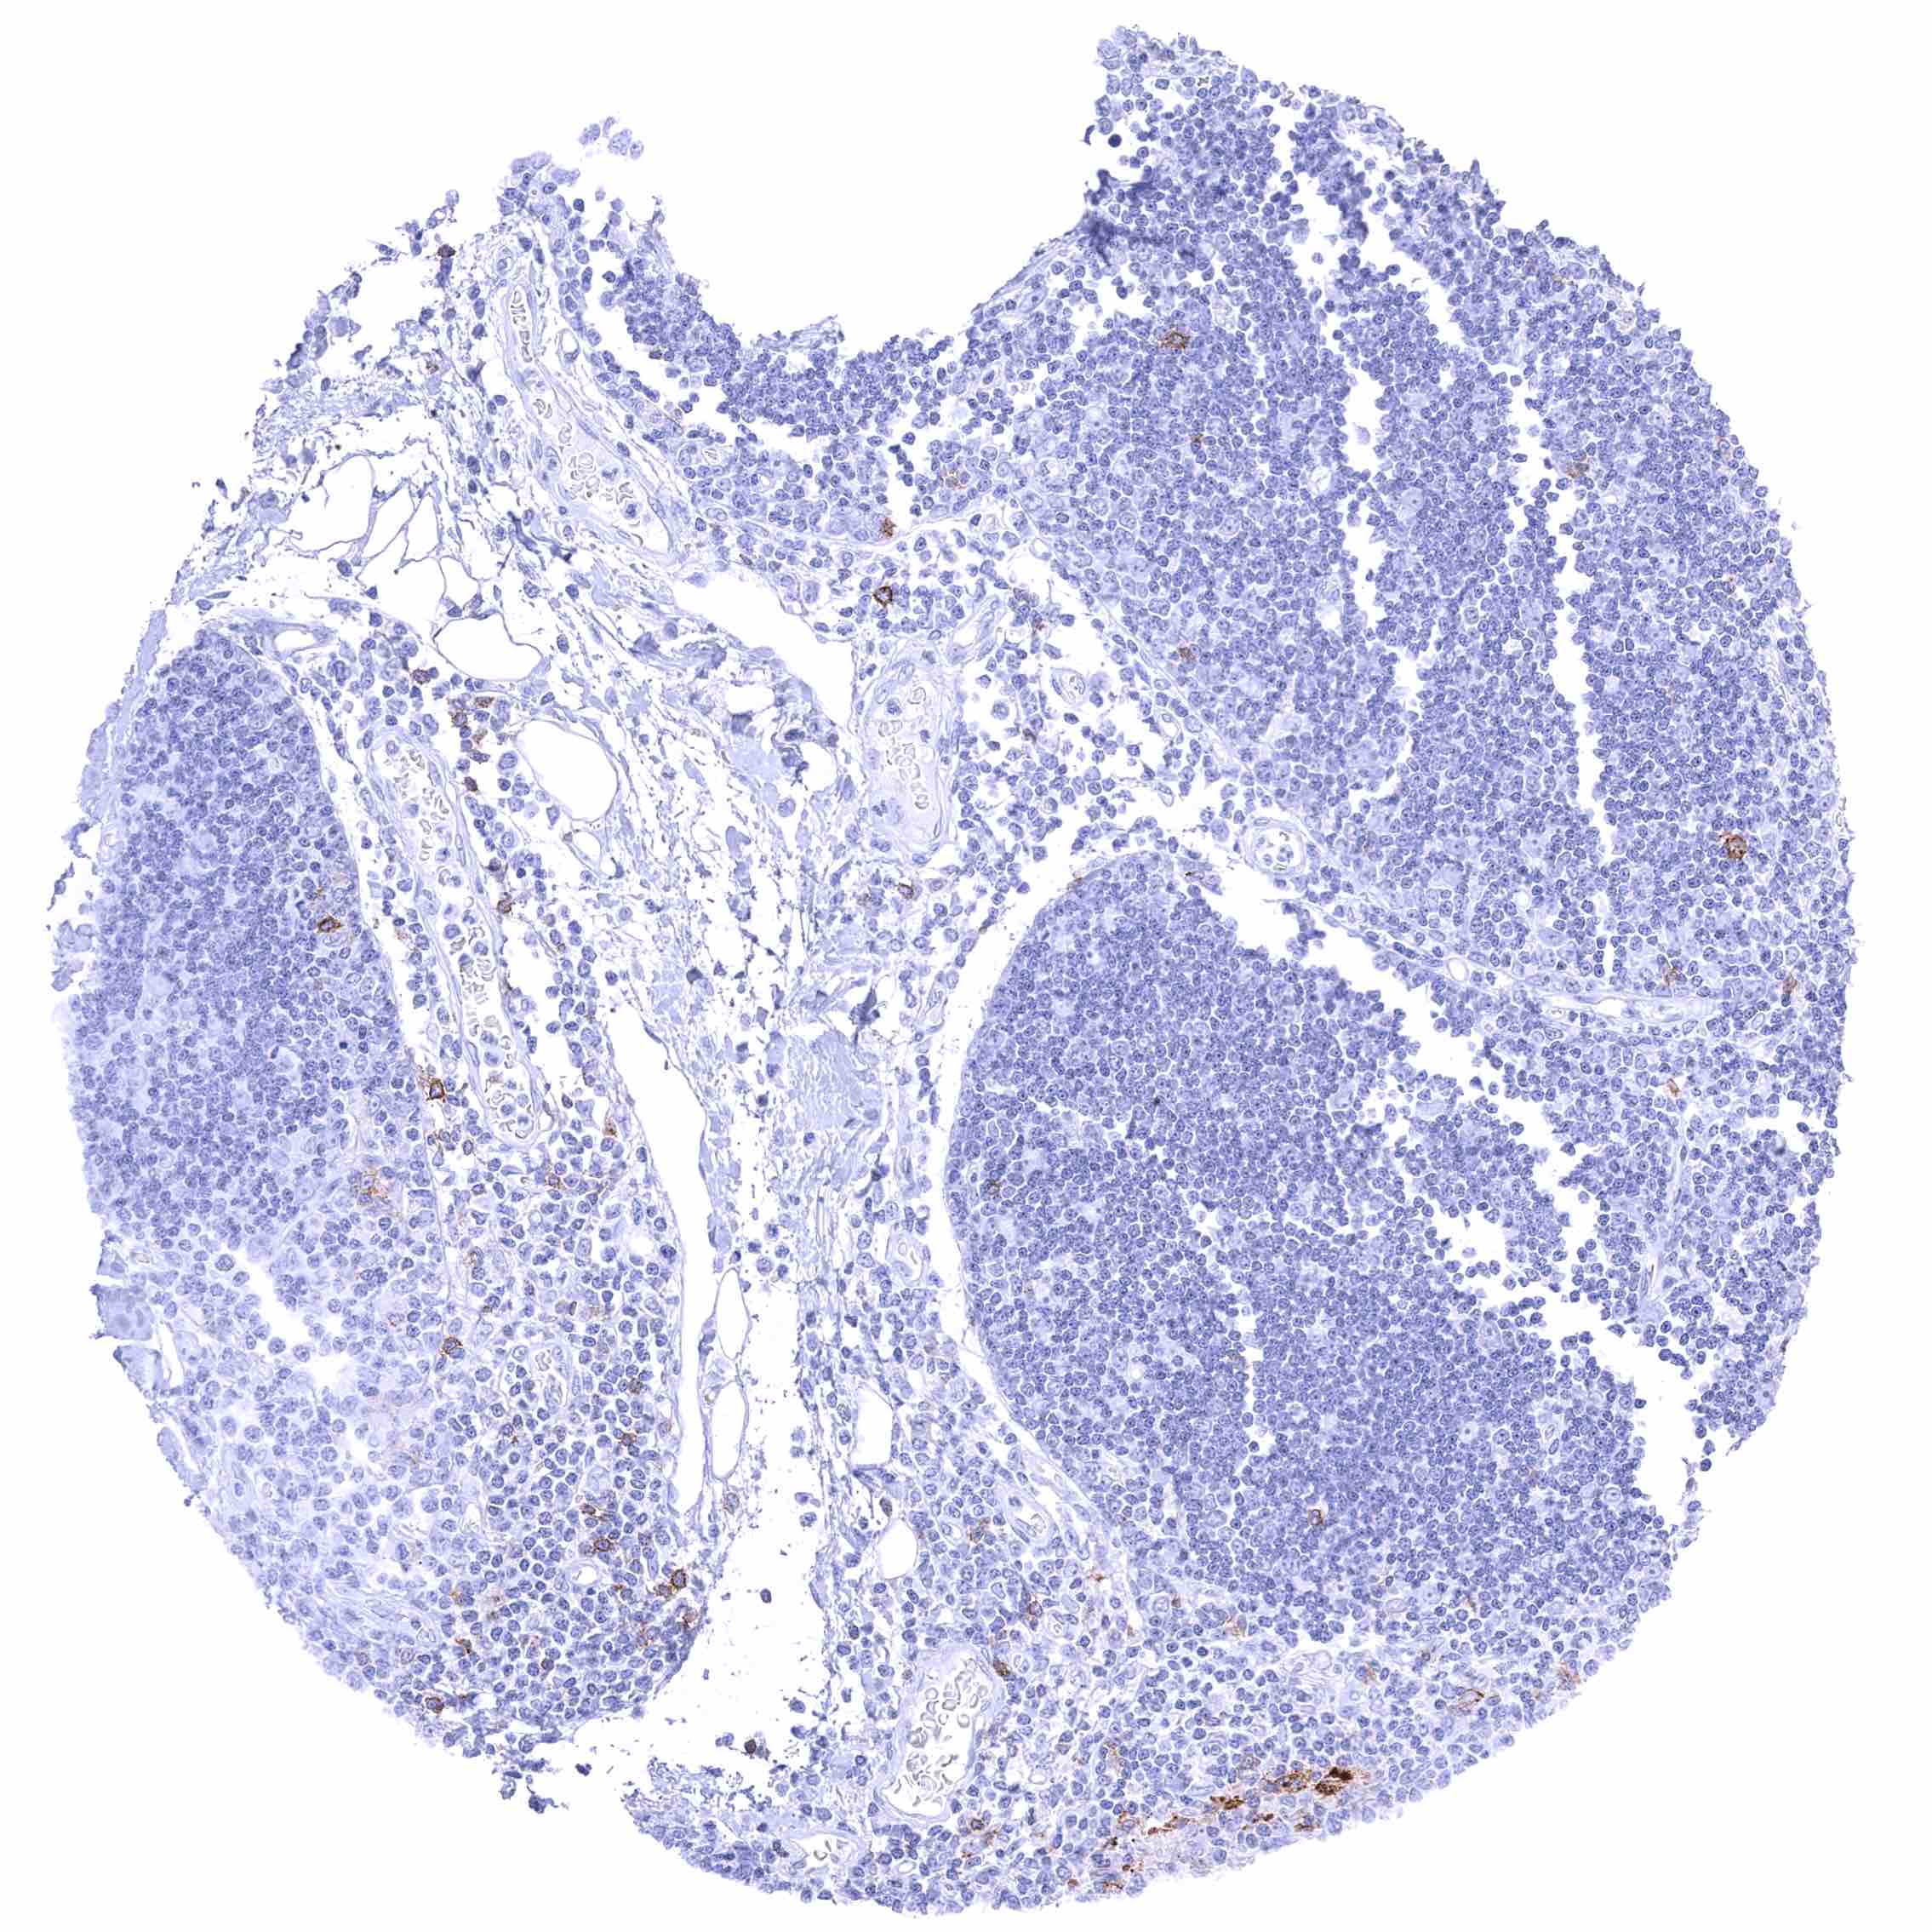

| Lymph node | Membranous CD70 staining of variable intensity in subsets of inflammatory cells (mostly lymphocytes). Most CD70 positive cells are interfollicular. | |

| Spleen | Membranous CD70 staining of variable intensity in a fraction of cells. | |

| Thymus | Membranous CD70 staining of variable intensity in a small subset of cells. | |

| Bone marrow/lymphoid tissue | Bone marrow | Weak CD70 staining in few cells. |